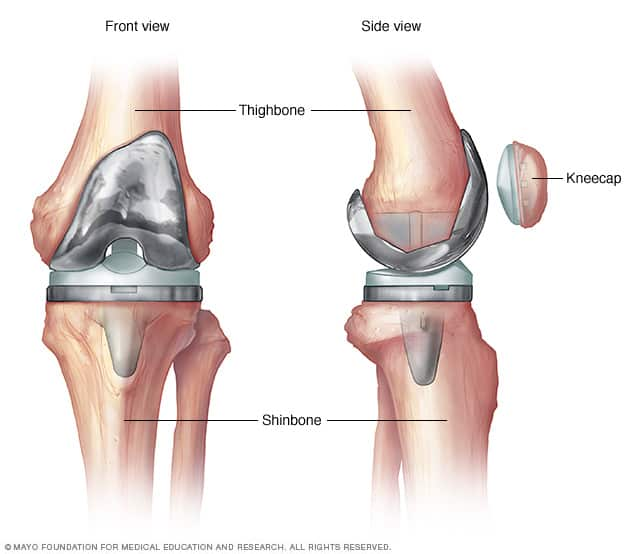

Knee replacement surgery — also known as knee arthroplasty (ARTH-row-plas-tee) — can help relieve pain and restore function in severely diseased knee joints. The procedure involves cutting away damaged bone and cartilage from your thighbone, shinbone and kneecap and replacing it with an artificial joint (prosthesis) made of metal alloys, high-grade plastics and polymers. In determining whether a knee replacement is right for you, an orthopedic surgeon assesses your knee's range of motion, stability and strength. X-rays help determine the extent of damage.Your doctor can choose from a variety of knee replacement prostheses and surgical techniques, considering your age, weight, activity level, knee size and shape, and overall health.

- During the procedure, the surgeon will remove bone and diseased cartilage from where your thigh bone (femur) and shin bone (tibia) meet at your knee joint.

- Those surfaces are then replaced with a metal implant. A piece of special plastic is normally used to replace the backside of the kneecap and finally, this same plastic material is placed in between the two metal parts.

- This gives both bones of your knee joint smooth surfaces again so they can flex and bend more freely and painlessly.